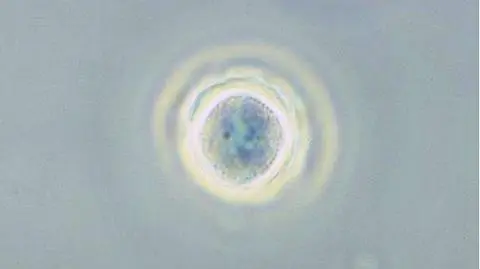

Według prof. Hadasia nie musimy martwić się o Naegleria fowleri, powinniśmy natomiast zwrócić uwagę na inne pasożyty, które mogą zagrozić naszemu zdrowiu. Przykładem jest Acanthamoeba, rodzaj ameby szczególnie niebezpiecznej dla osób zażywających kąpieli wodnych w soczewkach. Te pełzaki mogą przylegać do szkieł kontaktowych, później przenieść się na przednią powierzchnię oka. W efekcie czego człowiek musi zmagać się z długim i uciążliwym leczeniem.